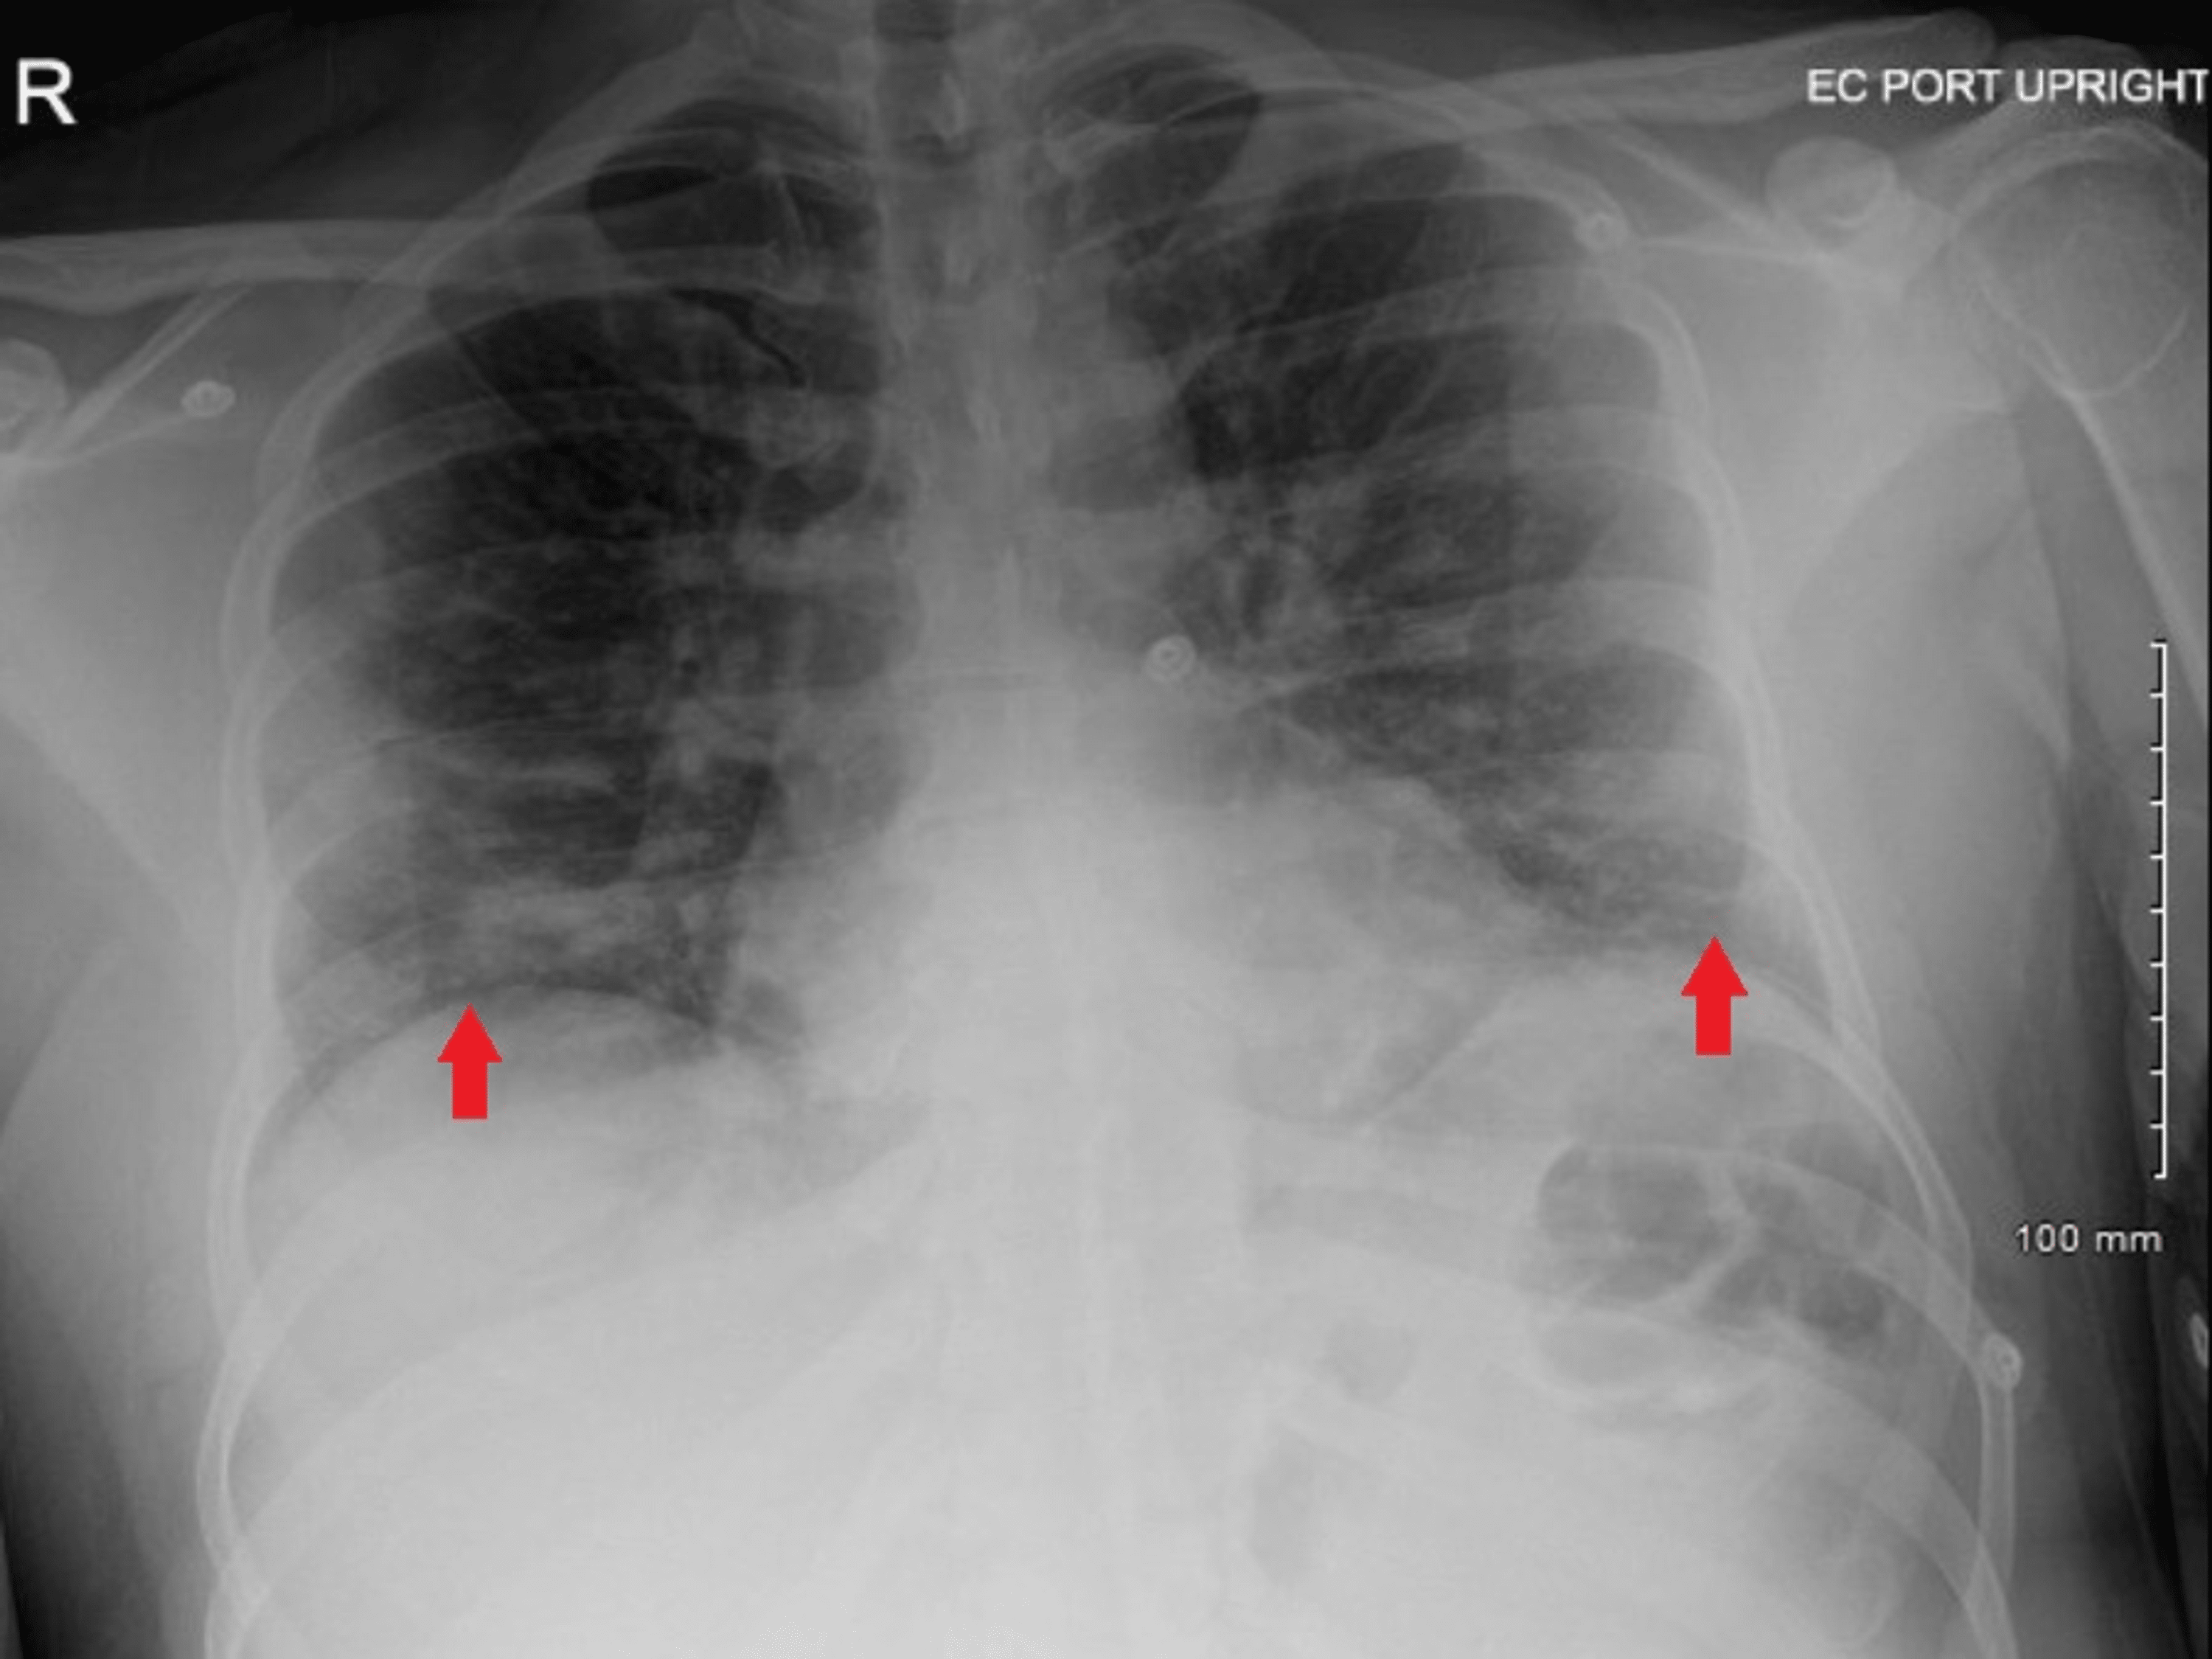

Incidental radiological diagnosis of rickets Emergency Medicine Journal Chest X Ray Findings In Rickets Right upper lobe collapse noted. this patient is presented with cough, chest x ray showed bronchiolitis. Incidental findings of active rickets features. periosteal new bone formation noted of the ribs along the mid axillary line. rickets results from impaired mineralization of growing bone due to alterations in calcium and phosphate. With treatment, there is a regression of. Chest X Ray Findings In Rickets.